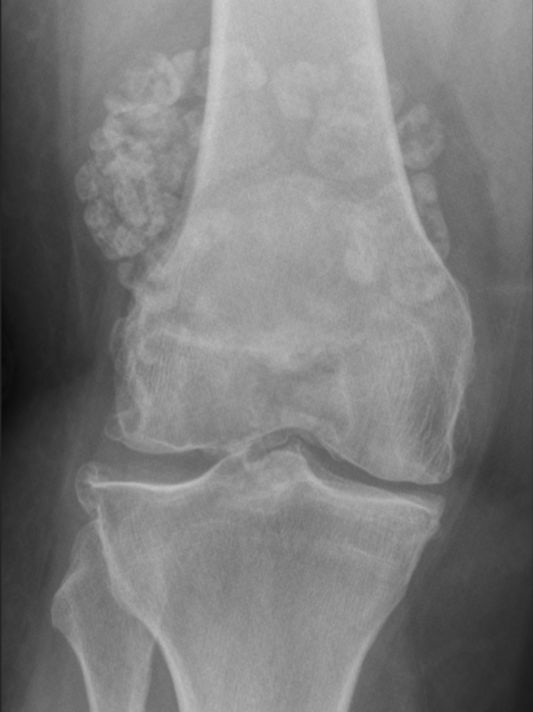

Synovial osteochondromatosis